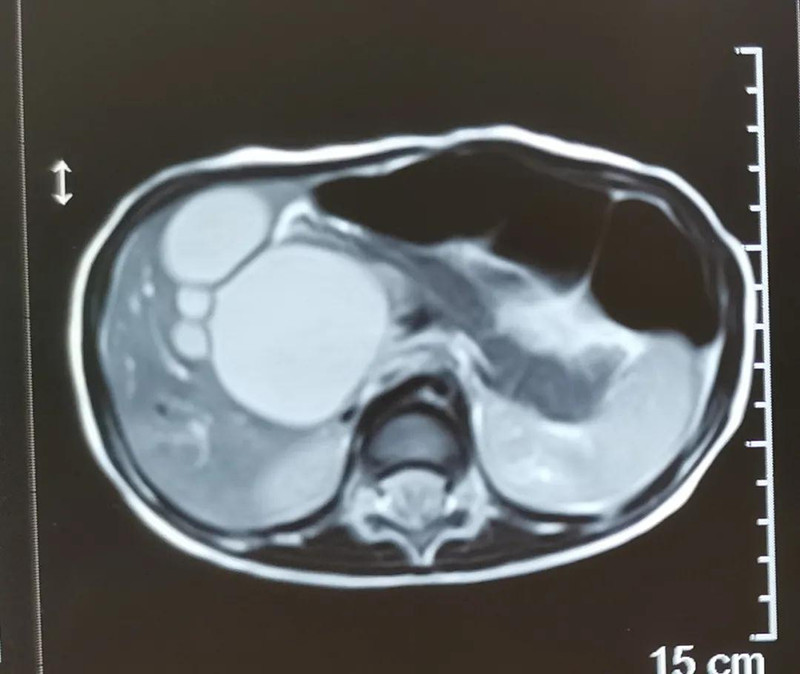

最近半个月,长春市26个月女宝馨馨(化名)脸色不好,全身发黄严重,还伴随发烧。9月23日,馨馨被家人带到a片网站 诊治。经检查,馨馨全身发黄是因为患有黄疸,而黄疸的出现是因为胆总管发生病变,“胆总管呈现囊性扩张,下边出口被堵住,胆汁进不到肠腔里,导致孩子出现黄疸、肝功不好、白土便症状。而且胆总管胀大后,还有癌变的风险,”普外、新生儿外科主任崔钊说,馨馨需要尽快手术。为了减少损伤,崔钊主任团队制定的方案是单孔腹腔镜下胆总管囊肿根治手术。

术前准备完毕。 9月25日,馨馨进入手术室。由崔钊主任带队,按照术前设计的方案,经过8个小时的奋战,手术成功了。馨馨肝总管以下病变的胆总管及胆囊全部切除,肝总管断面与肠管吻合接上,让胆汁直接流到肠腔里,帮助消化。如术后不出现胆瘘、肠瘘,没有梗阻,馨馨以后就可以正常生活了。目前馨馨恢复得很好,黄疸渐渐缓解,肝功正常,白细胞也降下来了,排气、排便都没问题,引尿管里也没有异常东西。